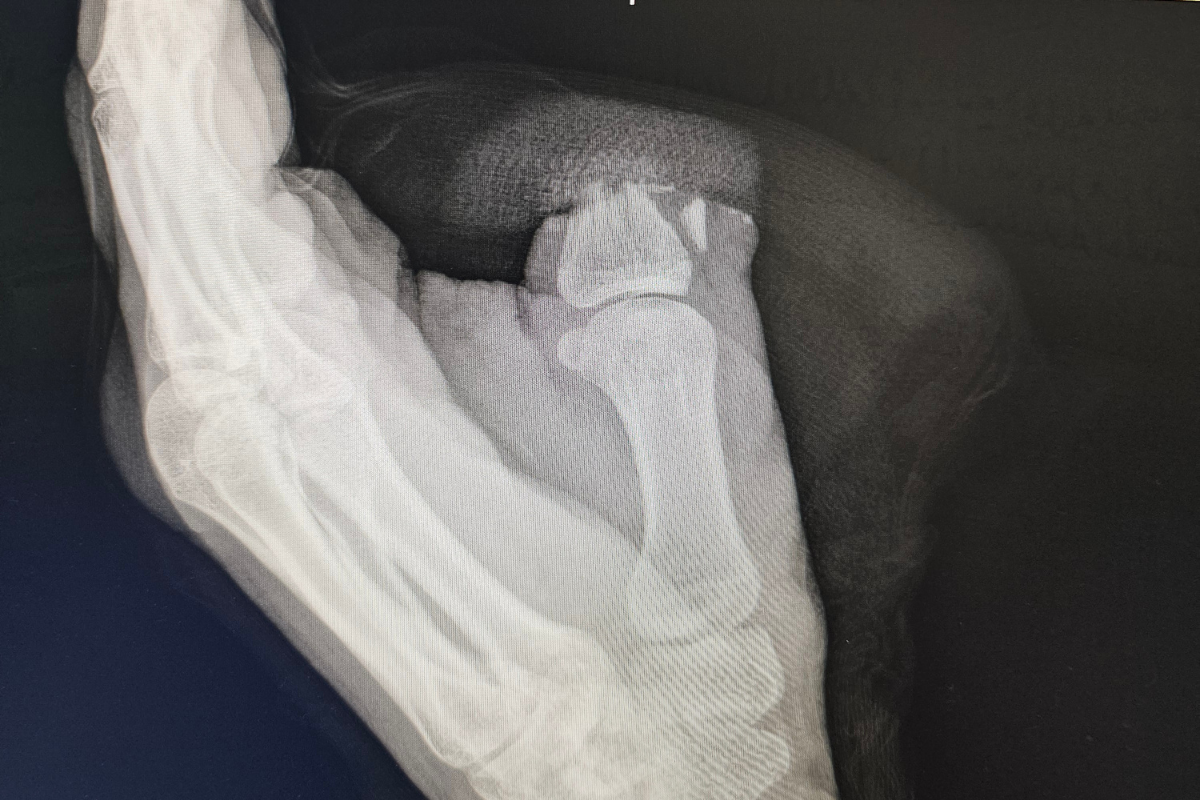

W Polsce nieformalnie funkcjonuje serwis replantacyjny, który opiera się na współpracy 11 ośrodków rozmieszczonych w całej Polsce, z których codziennie jeden szpital znajduje się w gotowości do konsultacji i ewentualnej replantacji kończyny. W ramach dyżuru 15 maja br. do Kliniki Ortopedii i Traumatologii Narządu Ruchu GUMed trafił 19-letni pacjent, który doznał amputacji kciuka podczas cięcia drewna. Do Szpitala im. M. Kopernika w Gdańsku został przewieziony transportem lotniczym z okolic Wrocławia. Od czasu urazu do rozpoczęcia operacji minęły zaledwie 4 godziny.

– Zespół Kliniki w składzie: lek. Zuzanna Duda oraz lek. Andrzej Wawruszczak przeprowadzili skomplikowaną operację, która składała się z zespolenia kości, ścięgien, mikrochirurgicznego zespolenia naczyń oraz nerwów. Zabieg trwał ponad 5 godzin – wyjaśniał prof. Mazurek. – Wykonanie replantacji to jednak dopiero pierwszy krok w długiej drodze do odzyskania sprawności. Przyszyta kończyna nigdy nie będzie w 100 procentach funkcjonalna. Pacjent wymaga długiej rehabilitacji, aby powrócić do codziennej pracy.

Replantacja polega na przyszyciu, czyli ożywieniu utraconej kończyny. Jest to niezwykle skomplikowana operacja łącząca w sobie techniki makro i mikrochirurgii. Pierwszy w Polsce tego rodzaju zabieg przeprowadził w 1971 r. w Trzebnicy prof. Kocięba. W gdańskiej Katedrze i Klinice Ortopedii pierwszą replantację przeprowadziłli w 1993 r. prof. Tomasz Mazurek, obecny kierownik jednostki oraz dr Adama Lorczyński.